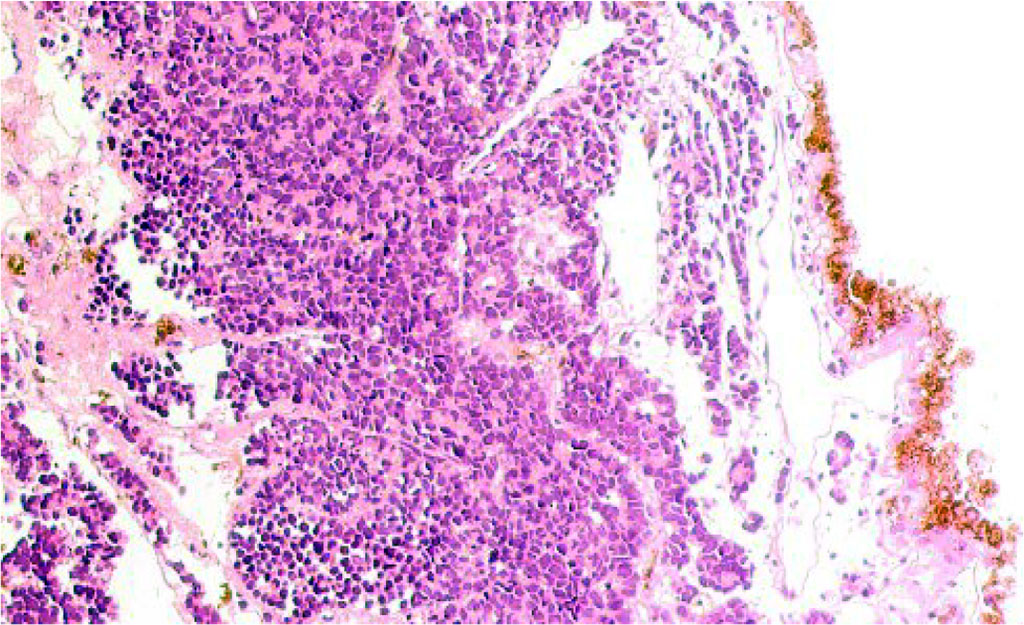

The general picture of retinoblastoma is characterized by depigmentation of the pigment epithelium and retinal detachment, represented by tumor cells, among which glial cells with a light chromophobic cytoplasm are identified in a small number (Figure 1). The pigment epithelium is located on a thickened basement membrane, which may border on germline neuroglia.

Figure 1 - Retina of a 9-year-old boy with retinoblastoma. Microphoto. Stained with hematoxylin and eosin. Magnification x100.